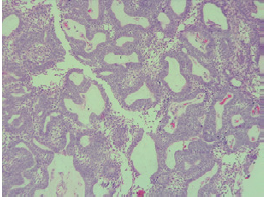

Biopsy was performed on the lesion of the scalp revealing ameloblastoma metastases; the subject was taken to surgery with wide local excision and free flap reconstruction. Surgical specimen pathology confirmed metastatic ameloblastoma and reported tumor-free section borders with margins of 14mm (Figure 2).

Histopathology study of resection of scalp metastases, follicular ameloblastoma without changes in the cell type of the primary tumor.

Figure 2: Histopathology study of resection of scalp metastases, follicular ameloblastoma without changes in the cell type of the primary tumor.

Source: Document obtained during the study.